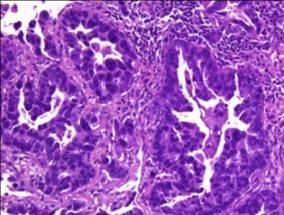

Si bien los fármacos contra la ruta de RAS conforman una parte importante del régimen terapéutico de muchos tumores, la búsqueda de inhibidores de RAS continúa "a pesar de que no está claro que los tumores no vayan a ser capaces de desarrollar resistencias contra estos tratamientos", subraya Sergio Ruiz, co-líder del estudio. "En nuestro trabajo mostramos que pueden desarrollarse teratomas (un tipo de tumor germinal) carentes de todos los genes RAS, si al mismo tiempo el tumor pierde la expresión de ERF", añade.